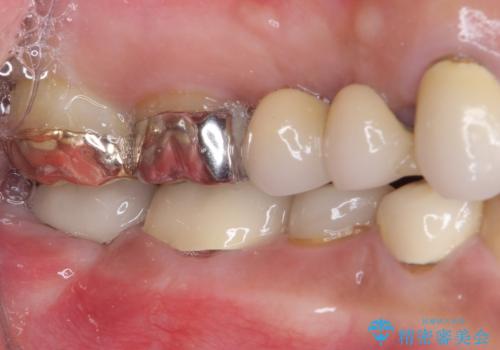

- 下顎の左右奥歯が痛みがあり、噛めないとのことで来院された患者様です。

左右ともに歯根が破折しており、抜歯が必要であったため、抜歯後にインプラント補綴治療を行うこととしました。

左上は当初治療予定ではありませんでしたが、クラウンの周りに汚れがたまっていることが気になってきたため、追加して治療を行うこととしました。

歯肉縁下にまで虫歯が及んでいたため、歯冠長延長術を行い、清掃性の改善を試みます。